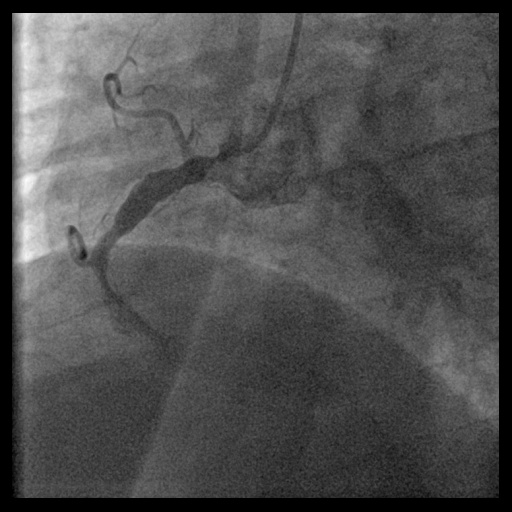

In 2020, he was admitted for NSTEMI. Emergency coronary angiography showed total occlusion of the right coronary artery (RCA). Initial attempts with a Fielder FC wire failed. Using a Gaia 1 and then Gaia 2 wire with a Progreat microcatheter, the lesion was successfully crossed. Predilatation was done with Euphora balloons (2.0 × 20 mm, 3.0 × 30 mm). Two Xience Sierra stents (3.5 × 38 mm, 3.5 × 15 mm) were deployed, followed by post-dilation with Accuforce balloons (4.0 × 20 mm, 4.5 × 15 mm).

Relevant Catheterization Findings

During this emergency catheterization, the right radial artery was accessed using a 20-gauge needle. A 6 Fr in 5 Glidesheath Slender® (Terumo Corp., Tokyo, Japan) was inserted. Coronary angiography was performed using Terumo 5 Fr Judkins catheters, revealing in-stent total occlusion of the RCA and patent left coronary artery (LCA).

In anticipation of a high thrombus burden, intracoronary Tirofiban was given to mitigate thrombotic risks. The Terumo 6 Fr in 5 Glidesheath Slender was exchanged for a 7 Fr in 6 Glidesheath Slender to accommodate larger catheters while preserving radial artery access. Using a 7 Fr SAL 1.0 guiding catheter (Medtronic, USA), the Fielder FC 0.014” × 180 cm wire (ASAHI Intecc, Japan) was advanced to the distal RCA. Despite GuideLiner (Teleflex, USA) support, the Terumo Eliminate aspiration catheter could not advance beyond the mid-RCA. StentBoost imaging revealed the wire had wound along the aneurysmal vessel wall and passing through a previous stent’s strut. Attempts to reshape the wire tip for re-entry into the stent center were unsuccessful. Although stent crushing was considered, navigating the wire through the stent without damage was prioritized. An Euphora balloon (2.0 × 20 mm) was inflated at 2 atm to seal the gap between the stent and vessel wall, enabling the passage of a Runthrough NS Floppy wire into the distal RCA. IVUS confirmed the wire’s position within the stent, which remained intact. The wire was exchanged for an ASAHI Sion Blue Extra-support wire with a Caravel microcatheter. Thrombus aspiration was completed using the Eliminate catheter. Post-dilatation was performed with a Conqueror NC balloon (4.00 × 20 mm, APT Medical), followed by NC Emerge and Accuforce balloons (4.5-6.0 mm). IVUS confirmed excellent stent apposition, and TIMI 3 flow was achieved.